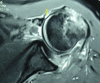

Irreducible shoulder dislocation is an uncommon event. When it does occur, blocks to reduction can include bone, labrum, rotator cuff musculature, or tendon. Concomitant rotator cuff tear at the time of initial dislocation is not an exclusive complication of anterior shoulder dislocation in the older population. Indeed, rotator cuff tear should not be excluded based solely on the patient's age. Rotator cuff interposition is not an uncommon complication after anterior dislocation of the shoulder. It should be suspected when there is incongruency of the joint and persistent subluxation on postreduction radiographs. If such incongruence or subluxation is seen, a computed tomographic (CT) or magnetic resonance imaging (MRI) scan must then be obtained to determine the nature of the interposed soft tissues. The key to treatment is early diagnosis and adequate imaging. Open reduction and repair of the rotator cuff should be performed. We present a technique for treating irreducible anterior shoulder dislocation caused by interposition of the subscapularis tendon. Both CT and MRI observations, along with intraoperative findings and surgical technique, are discussed.